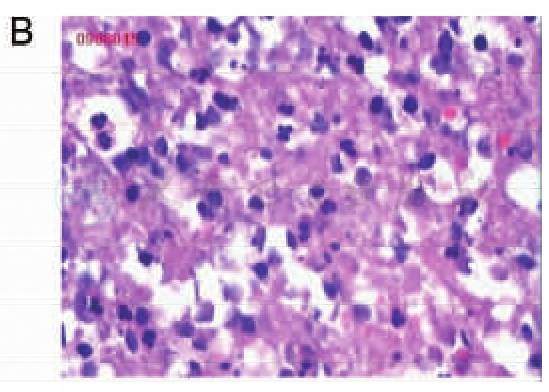

诊疗经过:入院后行MRI检查见右额顶占位病变,内有囊性坏死,增强扫描可见明显环形强化,考虑转移瘤可能性大(图1)。胸片、腹部B超结果未见明显异常。术前病例讨论结果:考虑胶质瘤或颅内转移瘤,不除外脑脓肿。入院第3天行右额顶开颅病变切除,术中穿刺见囊液呈脓性,冰冻结果为“脓性”。保护脑组织后予切除囊壁。术后病理:右额叶脑脓肿(图2)。

图1

图2 病例1大体标本及病理切片